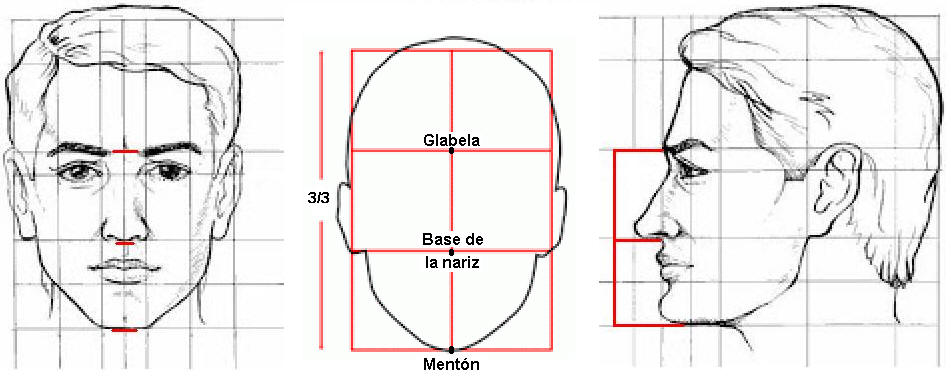

- Esto se realiza comparando la altura facial

inferior del paciente que es la línea que va del mentón hasta la

base de la nariz y debe ser proporcional al tercio medio de la cara

de nuestro paciente, que es el segmento

comprendido entre la base de la nariz y la glabela. (Regla de los

tres tercios)

"La dimensión vertical

oclusiva es la distancia entre el

maxilar y la mandíbula cuando los

rodetes están en contacto entre si

en posición de relación céntrica."

Ver imagen derecha